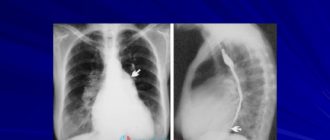

Что такое дилатационная кардиомиопатия: причины и симптомы, лечение и прогноз жизни Дилатационная кардиомиопатия —

Гипертрофия левого желудочка Под таким заболеванием, как гипертрофия левого желудочка имеется в виду такое